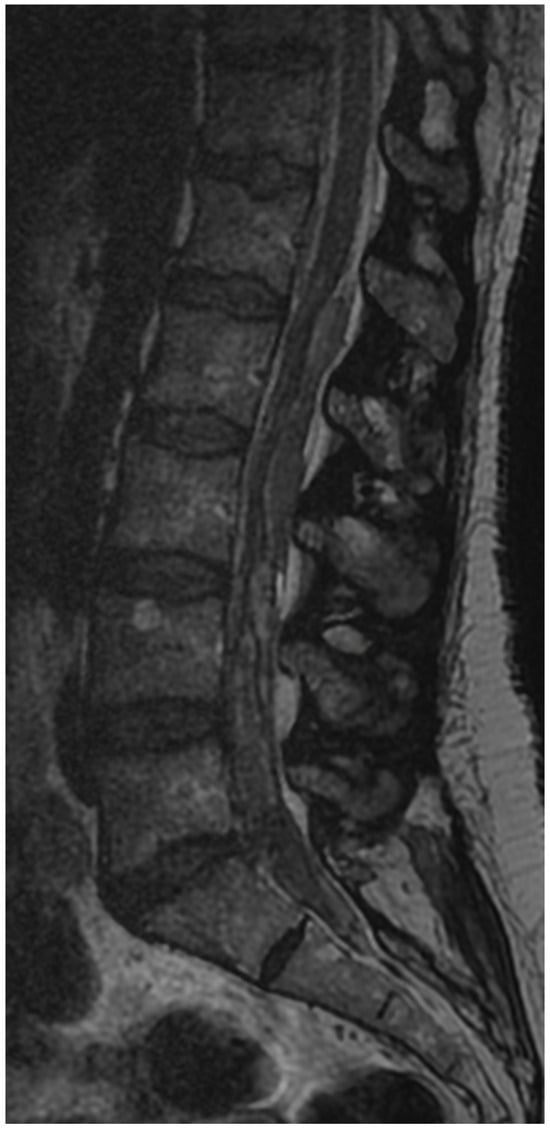

3.6. Case 3: Transient Paraparesis following Iatrogenic Vascular Fistula of the Dural Sac

- Case 3: Our review did not uncover any literature on intradural hematomas following endoscopic surgery. While there are isolated reports of such hematomas in other contexts [50,51], the dramatic progression and conservative management decision in our case are unique and underscore the need for cautious postoperative monitoring and possibly early intervention in similar future cases.